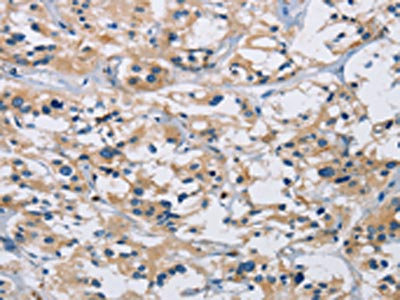

• The image on the left is immunohistochemistry of paraffin-embedded Human gastic cancer tissue using CSB-PA121041(IL17RB Antibody) at dilution 1/40, on the right is treated with synthetic peptide. (Original magnification: ×200)

• The image on the left is immunohistochemistry of paraffin-embedded Human thyroid cancer tissue using CSB-PA121041(IL17RB Antibody) at dilution 1/40, on the right is treated with synthetic peptide. (Original magnification: ×200)